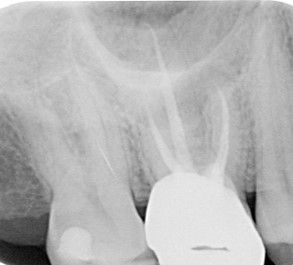

Cone Beam CT - Root Canal Treatment

We routinely use 3D X-rays to determine the extent of infection related to teeth, the root canal anatomy of the tooth, damage to the tooth from previous treatment and missed canals. This helps to determine whether treatment is likely to be successful and in conjunction with operating under the magnification of an operating microscope ensures that the fully root canal anatomy of the tooth is disinfected, increasing the success of treatments.